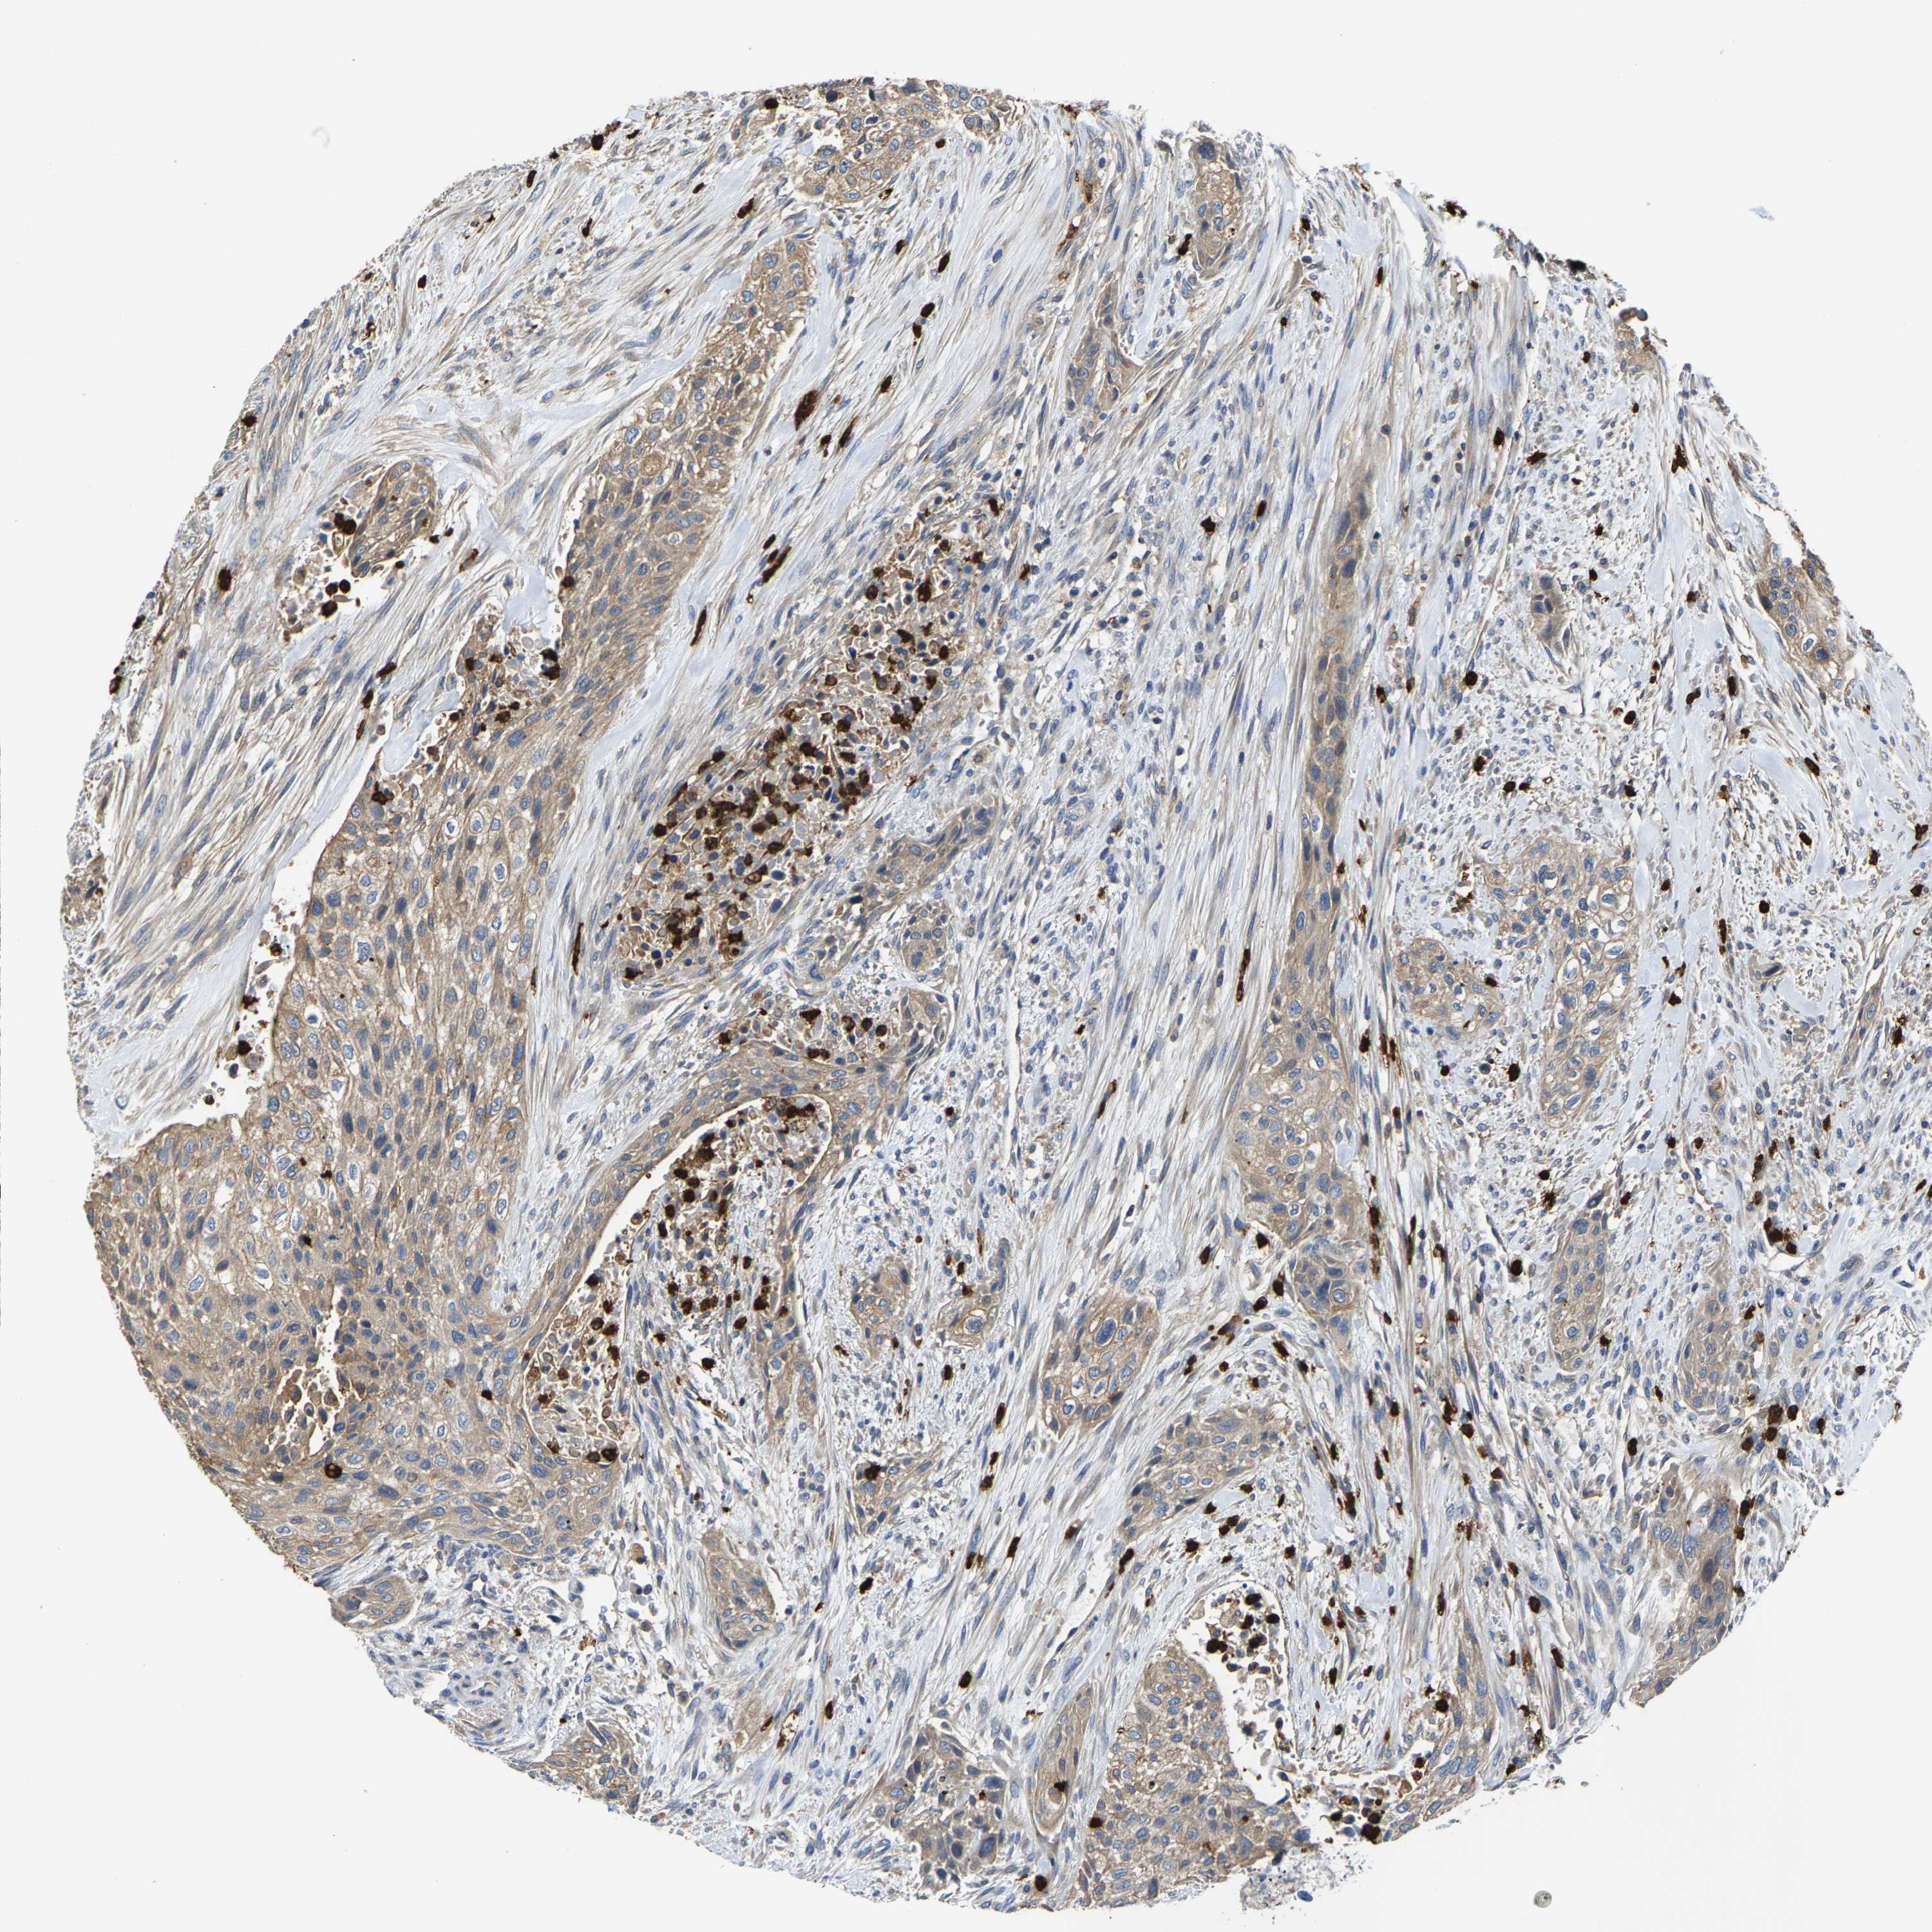

UROTHELIAL CANCER - Protein expressioni

A mouse-over function shows sample information and annotation data. Click on an image to view it in a full screen mode. Samples can be filtered based on level of antibody staining by selecting one or several of the following categories: high, medium, low and not detected. The assay and annotation is described here.

Note that samples used for immunohistochemistry by the Human Protein Atlas do not correspond to samples in the TCGA dataset.

Antibody stainingi

Antibody staining in the annotated cell types in the current human tissue is reported as not detected, low, medium, or high, based on conventional immunohistochemistry profiling in selected tissues. This score is based on the combination of the staining intensity and fraction of stained cells.

Each image is clickable and will lead to virtual microscopy that enables deeper exploration of all samples and also displays staining intensity scores, fraction scores and subcellular localization as well as patient and tissue information for each sample.

Antibody HPA019805

Antibody HPA020599

Antibody CAB004605

Staining

High

Medium

Low

Not detected

Intensity

Strong

Moderate

Weak

Negative

Quantity

>75%

75%-25%

<25%

None

Location

Nuclear

Cytoplasmic/membranous

Cytoplasmic/membranous,nuclear

Urothelial carcinoma, Low grade

Urothelial carcinoma, High grade